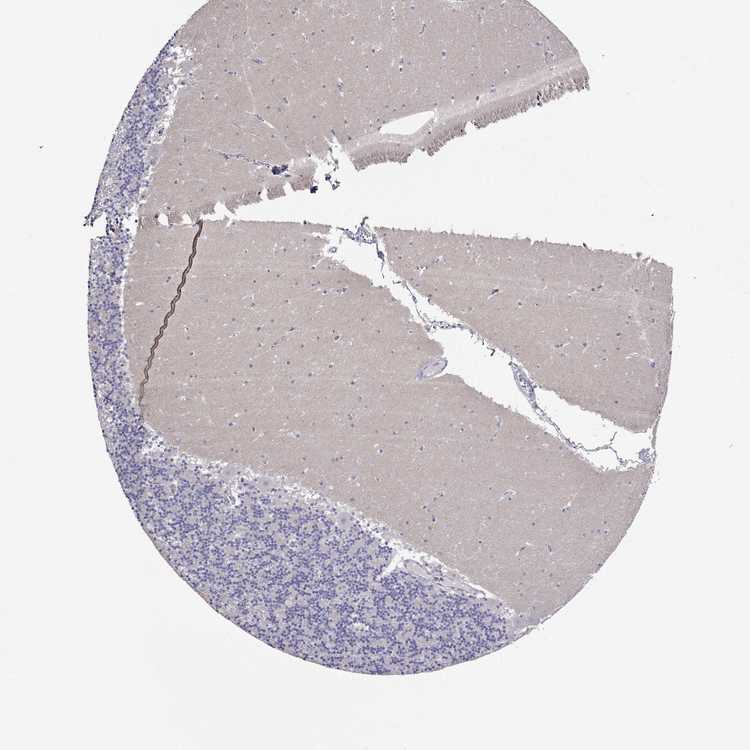

CEREBELLUM - Antibody stainingi

Antibody staining in the annotated cell types in the current human tissue is reported as not detected, low, medium, or high, based on conventional immunohistochemistry profiling in selected tissues. This score is based on the combination of the staining intensity and fraction of stained cells.

Each image is clickable and will lead to virtual microscopy that enables deeper exploration of all samples and also displays staining intensity scores, fraction scores and subcellular localization as well as patient and tissue information for each sample.

Antibody HPA074762Antibody CAB075684

Purkinje cells Not detectedNot detected

Cells in granular layer Not detectedNot detected

Cells in molecular layer Not detectedNot detected